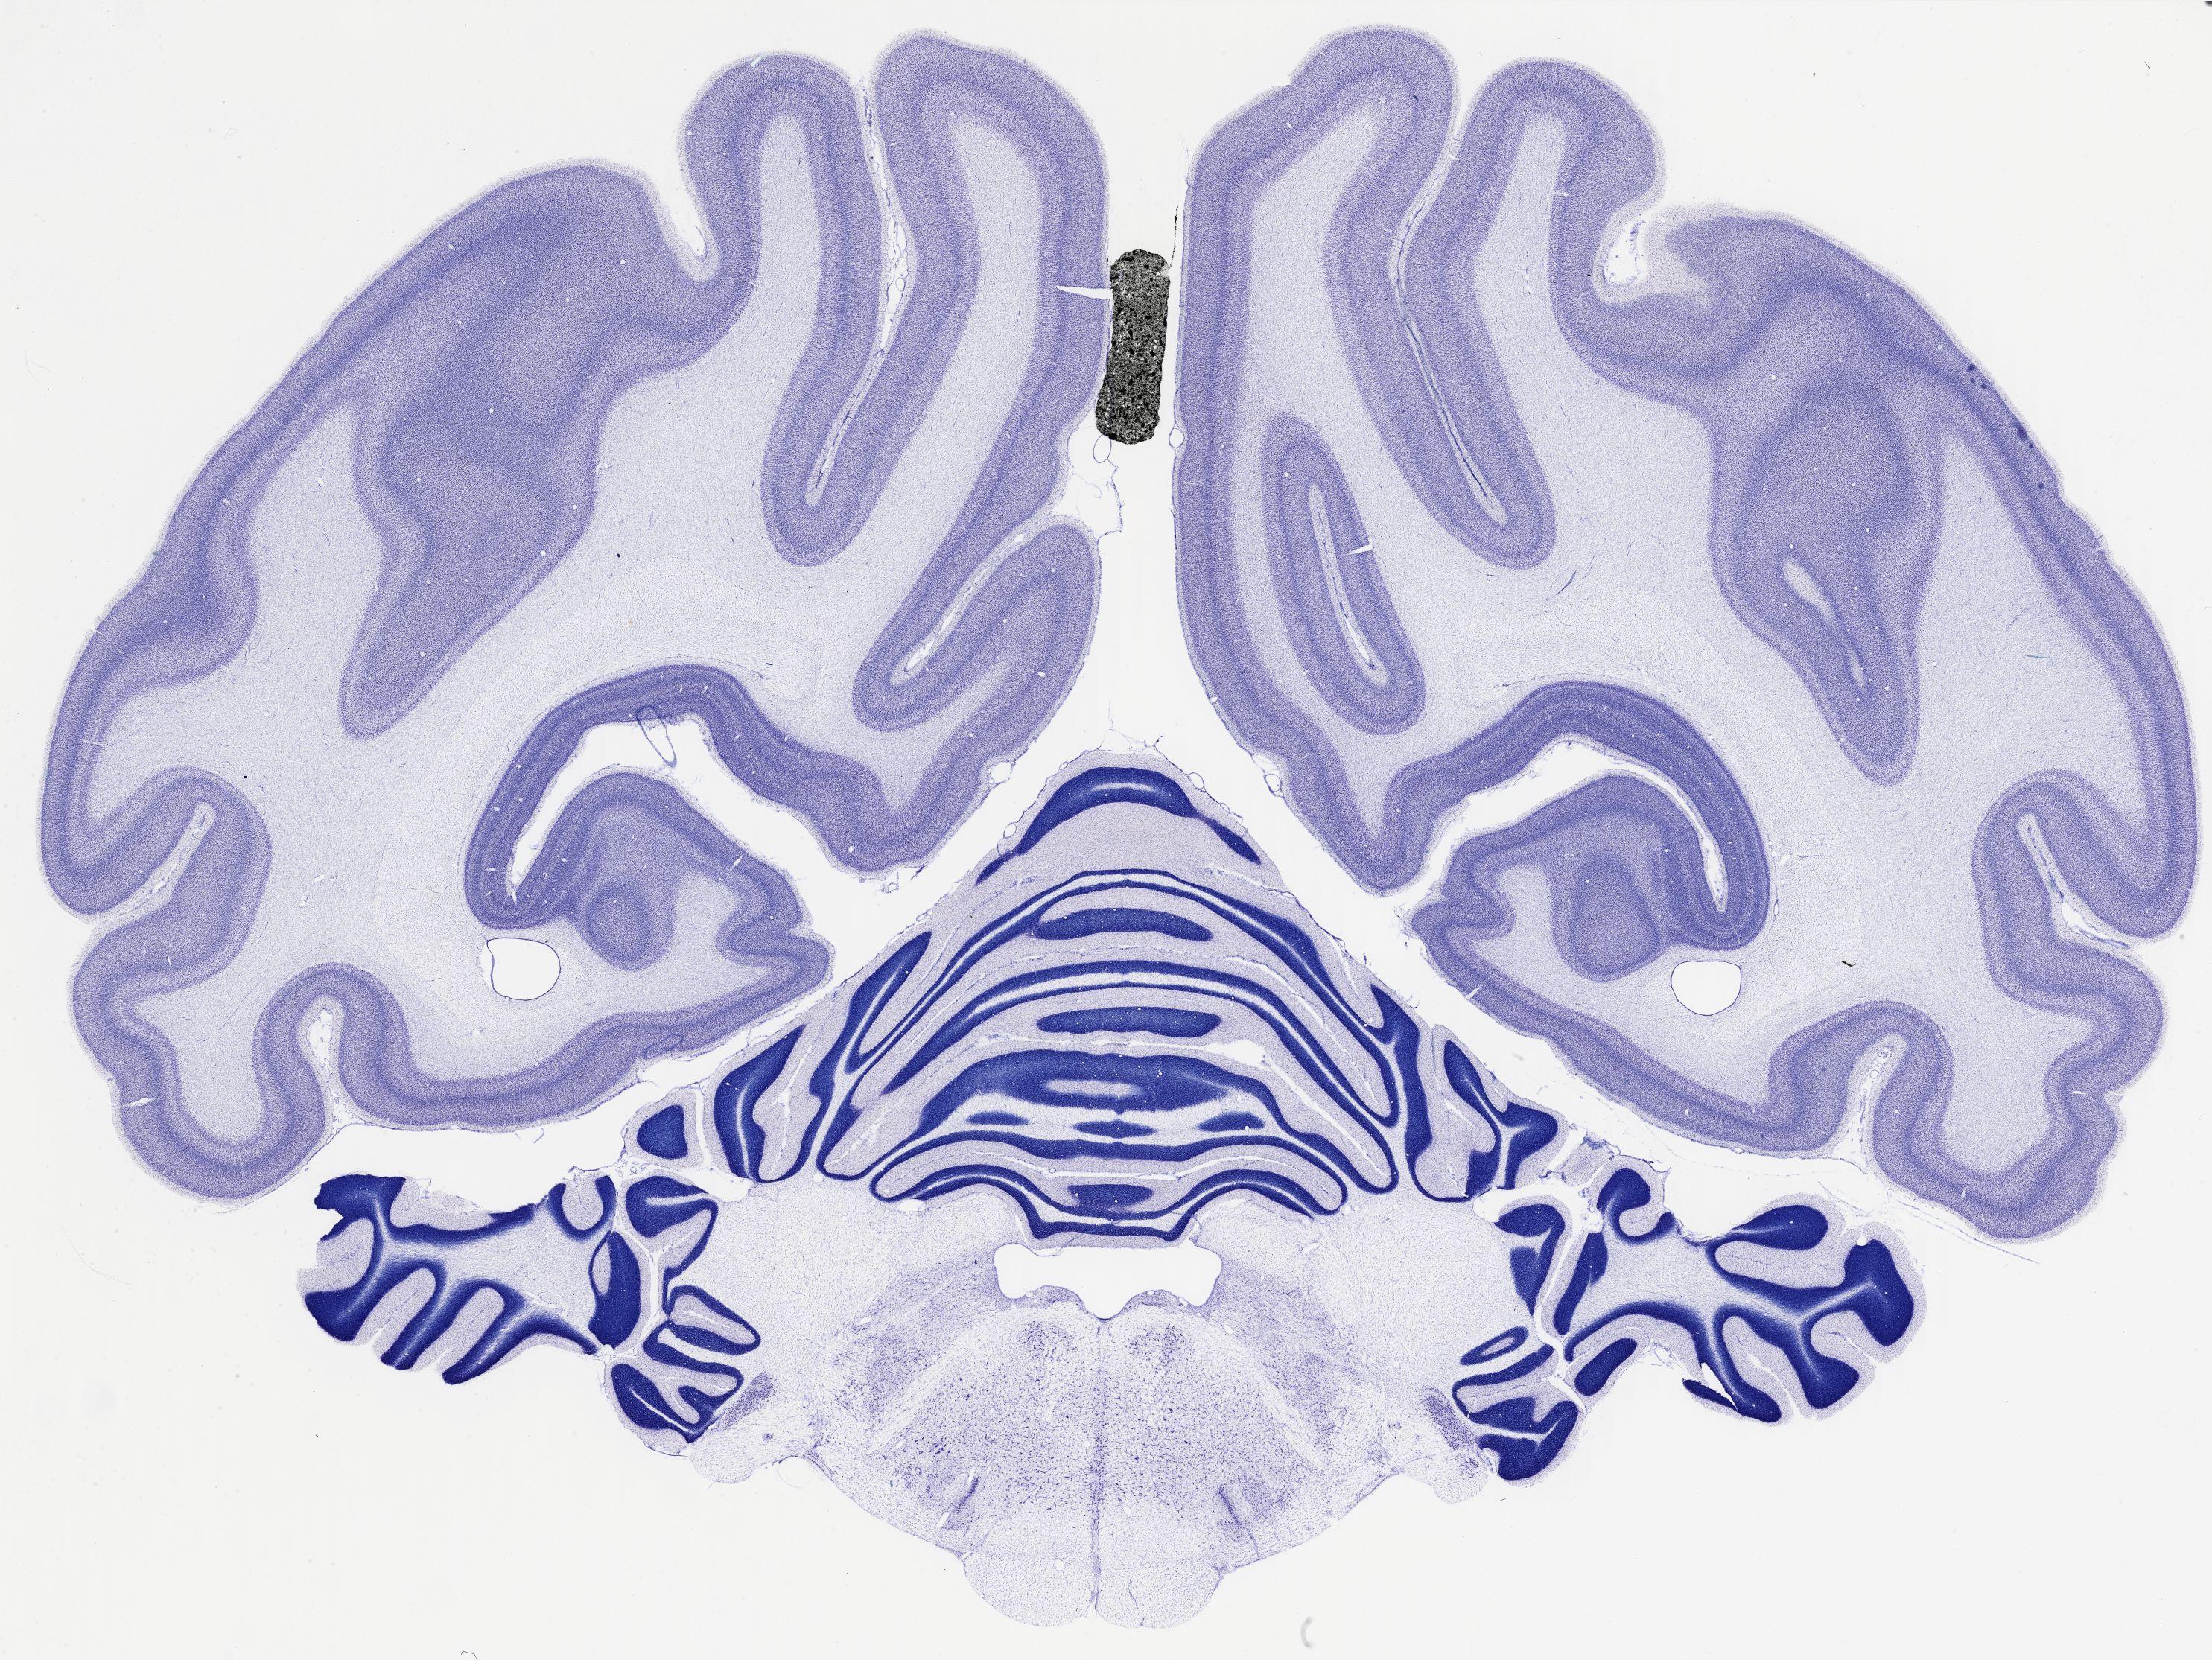

Datasets -> Chlorocebus Aethiops -> Nissl, coronal, histo, Whole-Brain, adult

[ Metadata ]   ·   Source: NeuroScience Associates

thumbnail

521